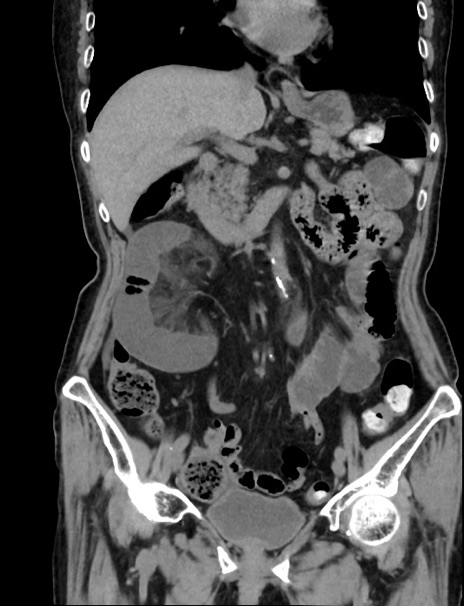

症例33(冠状断像)

【症例】70歳代 女性

【主訴】心窩部痛

【現病歴】延髄病変の精査・加療にて神経内科入院中。本日より心窩部痛あり。

【身体所見】右下腹部を中心に圧痛と反跳痛あり。

【データ】WBC 10900、CRP 0.02